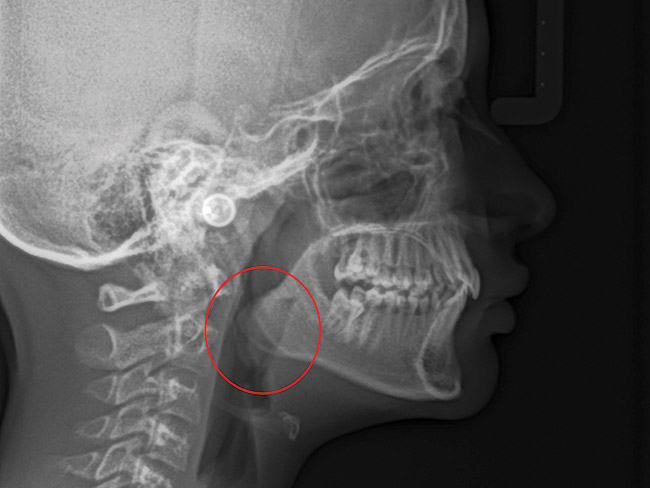

Tonsils and adenoids should be judged against the relative size of the airway rather than the absolute size of the lymphoid tissue46 (Figure 5 and Figure 6). Adenoids are located at the posterior of the nasal cavity on the roof of the nasopharynx (Figure 7). The normal distance from the adenoids to the soft palate for an acceptable airway should be at least 12 mm. For each millimeter decrease, the odds of the child snoring increase 1.61 times. Mouth breathers typically show a smaller upper airway dimension as well.47 The adenoid and tonsillar obstruction creates the trigger, but the deviate facial and neck muscle recruitment and tongue hypotonia cause the maldevelopment.48

The point of obstruction tends to determine the type of skeletal impact. Nasal obstruction from enlarged turbinates, blocked ostium maxillare, deviated septum, or nasal valve stenosis creates Angle occlusions of Class I, II, and III equally (Figure 8). The maxilla in these cases is positioned posteriorly and the mandible is posterior-inferior. The facial type is most commonly dolicocephalic. Blockage of the airway predominately by the adenoids will create growth patterns that yield mostly Class II occlusions and anterior open bite with both jaws located posterior-inferiorly. Facial type is again dolicocephalic with the typical long-thin “adenoidal” face49 (Figure 9 through Figure 12). If the tonsillar tissue is responsible for the airway obstruction, the tongue will have an abnormal resting posture. Class III occlusions will be more common with the maxilla normal or posterior placed (Figure 13 through 15). The tongue may direct the mandible anteriorly or, because the tongue is not in the roof of the mouth driving A point anterior, the maxilla will become bimaxillary retrusive.50 In some cases, the anterior posture of the tongue will create an open bite. This is incorrectly referred to as a tongue thrust. The impact from a thrust does not alter the tooth position. Long-term, low forces cause tooth movement. The posture of the tongue against or between the anterior teeth due to the excessive tonsillar size creates the open bite (Figure 16 and Figure 17). Facial types in this group are more brachyfacial. Lastly, if the airway is blocked through a combination of factors, the Angle classification will be either Class II or III. The maxilla will be in a normal location and the mandible will be the affected arch (Figure 18). These craniofacial changes are not restricted to OSA; all SDB will create unique alterations depending on the patient compensation. Children with UARS have been reported to display high, narrow palates, dolicofacial form, and a Class II malocclusion, indicative of largely adenoidal blockage.51